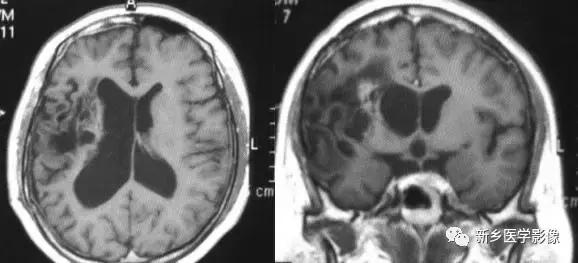

(3)无脑回和巨脑回

无脑回和巨脑回是一组因神经元移行异常所致的脑回发育异常。巨脑回也称平滑脑。巨脑回指有部分脑回存在,这些脑回异常增大增宽.脑沟变浅。巨脑回主要位于额、颞部。无脑回上要位于顶、枕部。

临床上,无脑回和巨脑回畸形患儿均表现有小头畸形和轻微的面部异常,完全无脑回畸形常在两岁前死亡.不完全无脑回畸形存活常能长期。

CT和MR均能够很好显示无脑回和巨脑回畸,表现为大脑半球表面几乎呈光滑状,仅可见少数宽阔、粗大、平坦的脑回,脑沟缺如.脑灰质增厚,脑白质变薄,灰白质分界面异常平滑,见不到白质向灰质内伸入的现象。常见透明中隔腔存在.侧脑室扩大,蛛网膜下腔增宽。